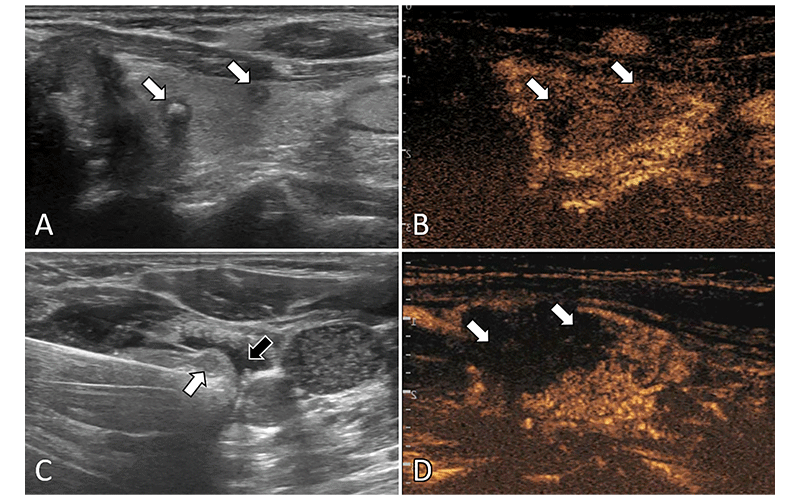

Ultrasound (US) images in a 57-year-old female patient with multifocal papillary thyroid carcinoma (PTC). (A) Routine US scan shows two hypoechoic PTC nodules (arrows) in the left lobe. (B) Preablation contrast-enhanced US image shows hypoenhancement in the arterial phase (arrows). (C) Isolating fluid (black arrow) is used to protect the muscles beside the nodule (white arrow) during the ablation. (D) Postablation contrastenhanced US image shows no enhancement in the original tumor zone (arrows).